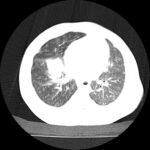

Infant tuberculosis (TB) is a rare but potentially deadly infection and difficult to diagnose, especially in infants who may present with non-specific symptoms. Here, we report a case of an United States-born term infant with community-acquired miliary TB and no confirmed TB exposure history. The patient initially presented with respiratory distress at seven weeks of life with chest radiograph showing a right lower lobe (RLL) infiltrate. After failing multiple courses of treatment for community-acquired pneumonia and developing growth faltering, the patient had imaging findings suggestive of TB infection with CNS involvement. The diagnosis of TB was confirmed by QuantiFERON and purified protein derivative (PPD). In infants who fail conventional treatment for bacterial pneumonia, the differential should be broadened to consider alternative etiologies. Additionally, brain imaging should be performed in cases of disseminated TB despite negative cerebrospinal fluid (CSF) studies since these patients are at high risk of central nervous system (CNS) involvement.